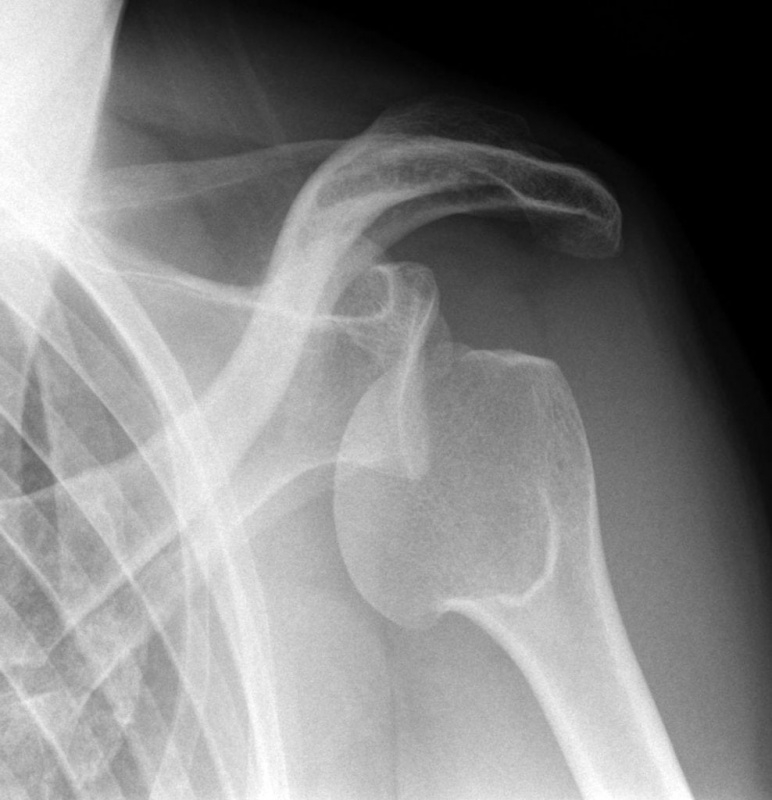

НА ЯКИЙ СУГЛОБ ВКАЗУЄ СТРІЛКА НА РЕНТГЕНОГРАМІ? КІСТКИ ЯКОГО ВІДДІЛУ СКЕЛЕТУ ВІН З'ЄДНУЄ?

варіанти відповідей

ГРУДНИННО-КЛЮЧИЧНИЙ С.

ПЛЕЧОВИЙ С.

НАДПЛЕЧОВО-КЛЮЧИЧНИЙ С.

АКРОМІАЛЬНО-КЛЮЧИЧНИЙ С.

КІСТКИ ВЕРХНЬОЇ КІНЦІВКИ

КІСТКИ ТУЛУБА І ВЕРХНЬОЇ КІНЦІВКИ